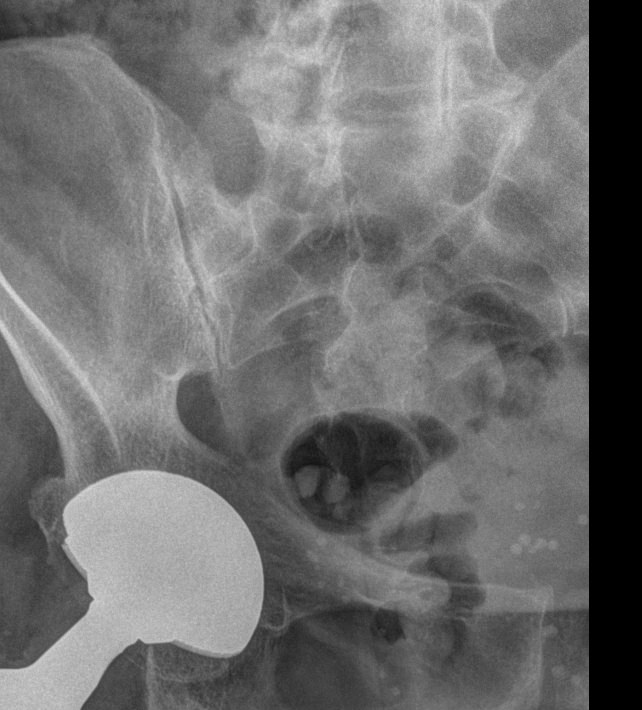

Для диагностики сочленения прибегают к рентгенографии, причем снимки делают с обеих сторон, чтобы можно было сравнить здоровую и измененную сторону. Для более детального исследования применяют МРТ.

Что покажет рентген крестцово-подвздошного сочленения?

• Изменения в состоянии рентгеновской суставной щели ― расширение, сужение, сращение;

• Изменения суставной поверхности ― нечеткость контуров, уплотнение, эрозии;

• Изменения в костной ткани ― участки деструкции, воспаление, склероз;

• Наличие кист и других новообразований;

• Изменения в мягких тканях